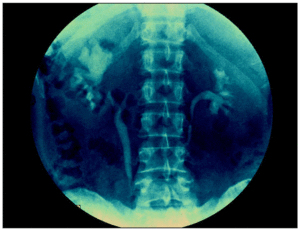

Se practicó un nuevo análisis de orina con estudio parasitológico cuyo resultado fue negativo. La piuria abacteriana persistía, por lo que se realizaron tinciones de Auramina y Ziehl-Neelsen con las que se observaron abundantes bacilos ácido-alcohol resistentes (BAAR). La prueba de Mantoux resultó positiva (15 mm). En el cultivo en medio de Löwenstein-Jensen, se aisló e identificó Mycobacterium tuberculosis. En la radiología de tórax, no se observaron lesiones y en la urografía intravenosa se constató ectasia pielocalicial en riñón izquierdo, con deformación de papilas y atrofia del parénquima renal (fig. 3). La ecografía renal mostraba hígado y vías biliares normales, y la imagen del riñón izquierdo era compatible con pielonefritis crónica.

Figura 3. Urografía intravenosa. Se aprecia ectasia pielocalicial en riñón izquierdo.